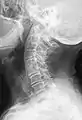

Block vertebrae of the cervical spine (vertebrae 4 and 5). Probably based on degenerative or inflammatory changes.